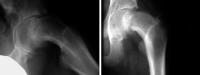

Hüftgelenk

Abbildung 1: Linkes Hüftgelenk. St. p. eitriger Coxitis: Femurkopf und Schenkelhals sind "weggeschmolzen", das Femur stützt sich nur an der Darmbeinschaufel ab.